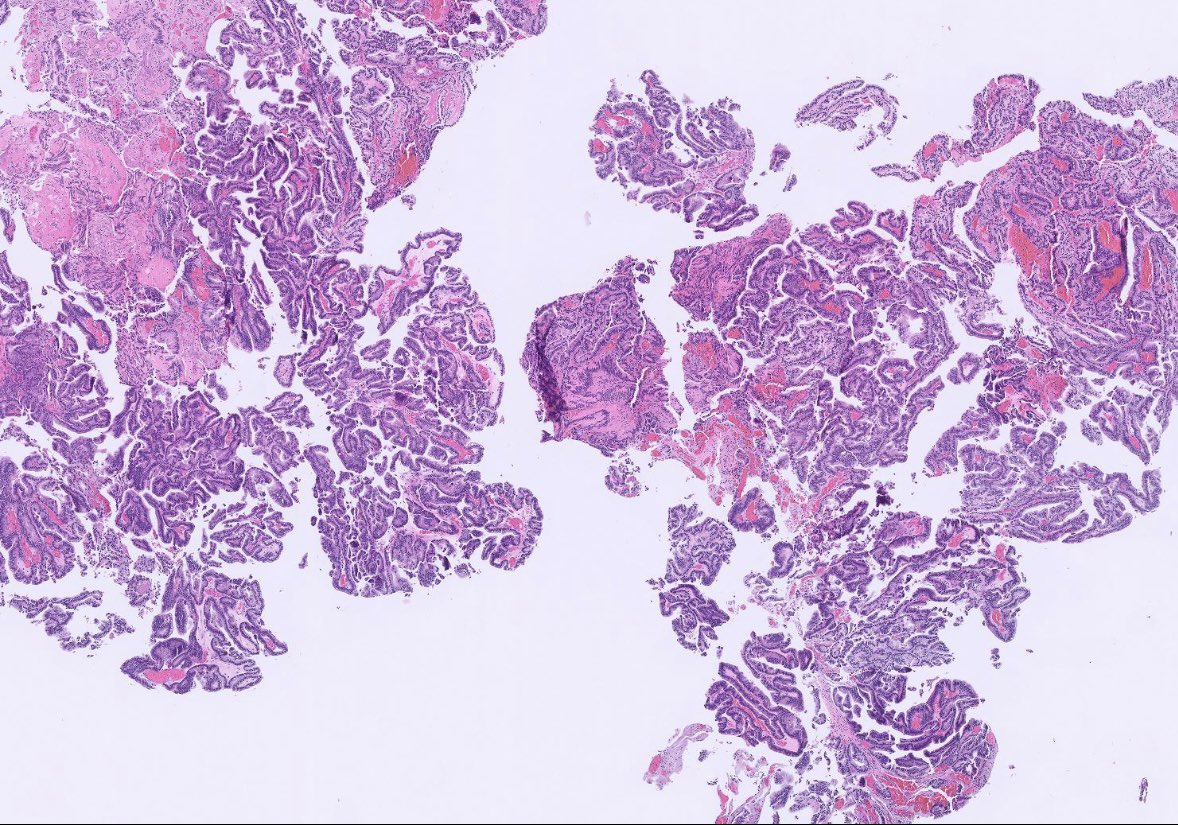

After a long Twitter hiatus because... life... I'm back to bring you this endometrial lesion in a 42 yo woman with abnormal uterine bleeding. Hysteroscopy showed an endometrial polyp in the lower uterine segment #GynePath #GynPath #PathTwitter